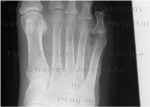

Информативность .снимков. На снимках видны кости предплюсны: таранная, ладьевидная, кубовидная и клиновидные, суставные щели между ними. Раздельно отображаются все кости плюсны и фаланг, видны их переднебоковые и зад небоковые поверхности. Прослеживаются рентгеновские суставные щели плюснефаланговых и межфаланговых суставов (рис. 449). .png)

В этом случае снимки стоп в косых проекциях по сравнению с другими снимками являются наиболее информативными для выявления переломов плюсневых костей и фаланг (рис. 450, а, б).